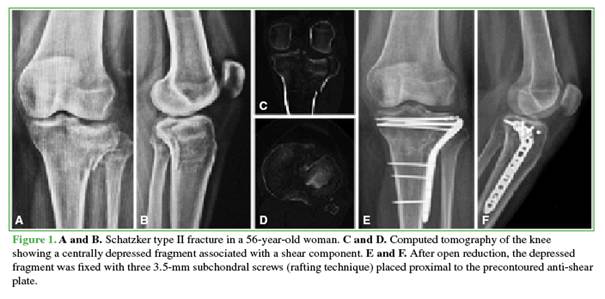

After reduction, preliminary fixation was performed with Kirschner wires. In the rafting technique group (Figure 1), definitive fixation was achieved with 3.5-mm subchondral screws placed through the plate when its design allowed adequate subchondral positioning. When this was not possible, the screws were placed proximally outside the plate.

In the other procedure, the articular surface was restored with impacted bone allograft introduced through a distal window; two cannulated screws (4.5 or 6.5 mm) were then inserted, followed by additional impaction and filling with allograft to occupy the metaphyseal defect (Figure 2).